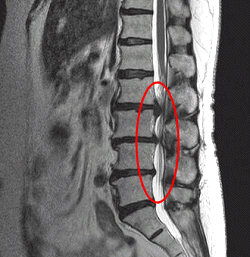

ヘルニアの診断を病院で受けた患者さんが、

MRIの写真を持参されたので考察してみました。

腰の骨ヘルニアのMRI画像